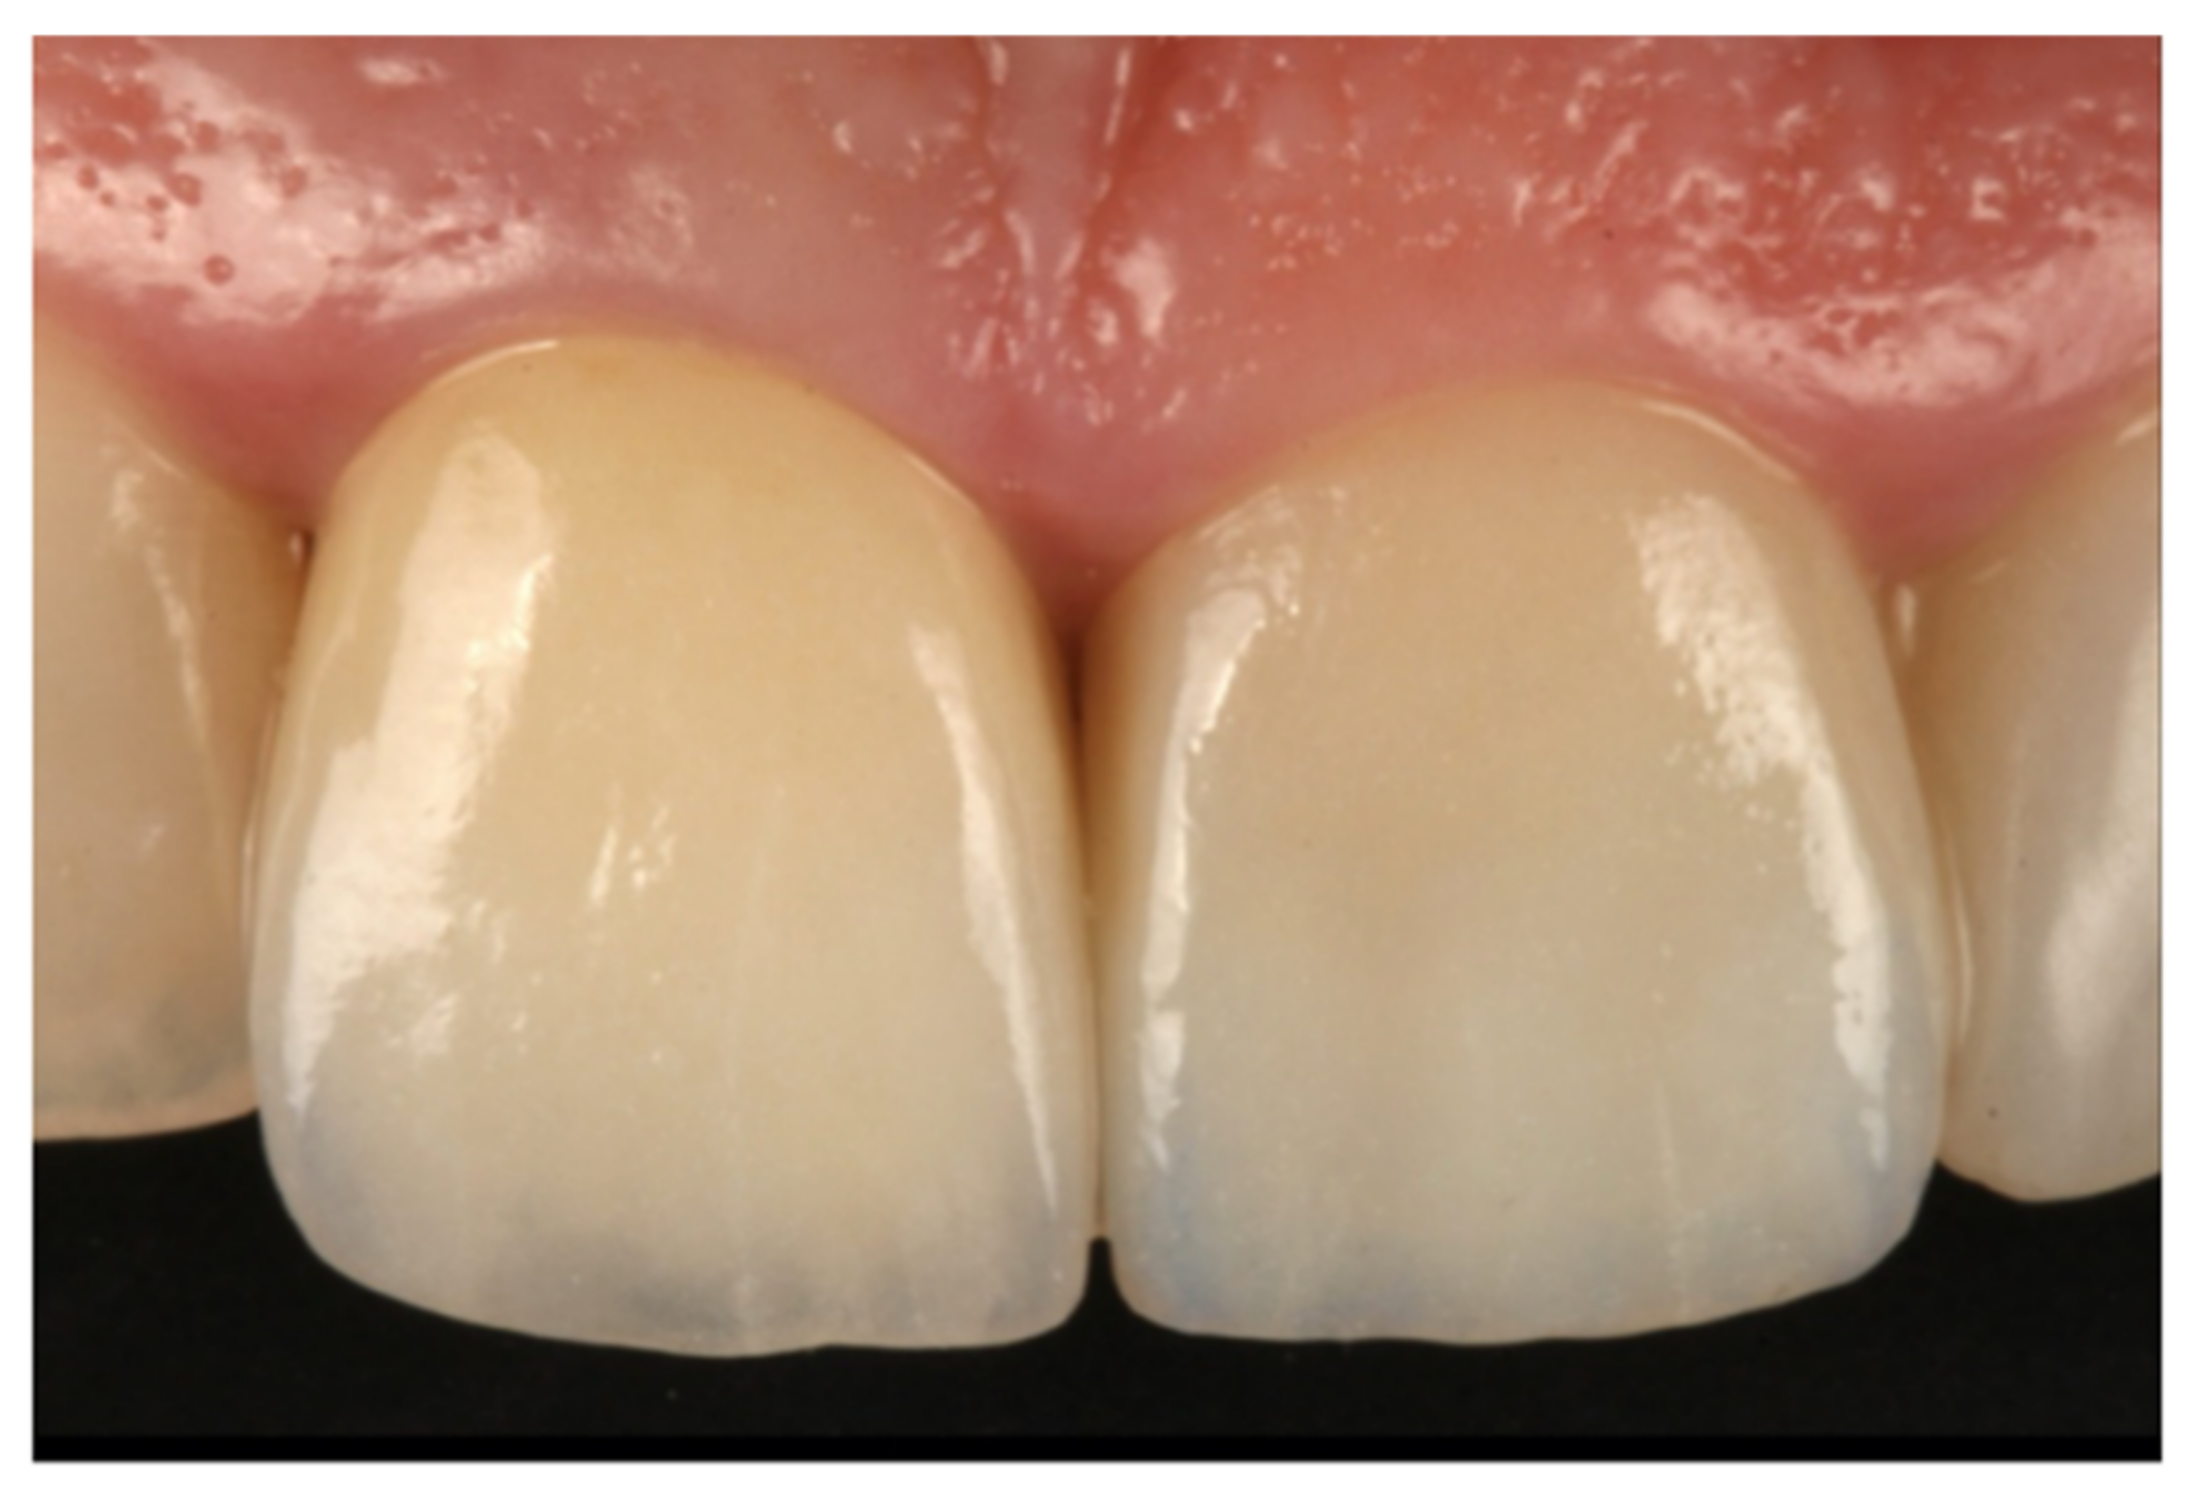

- Teeth treated with this technique presented improved plaque indices, stable probing depths, increased gingival thickness, and stable gingival margins over the 6-year follow-up.

- Treatment with a fixed prosthesis using the BOPT technique has a positive impact on patient satisfaction, especially in cases concerning the re-treatment of old fixed prostheses. This fact is due to the esthetic improvement not only of the restoration but also of the surrounding tissues, as it improves gingival quality by thickening the tissue, thus preventing gingival recession.

- Agustín-Panadero, R.; Serra-Pastor, B.; Fons-Font, A.; Solá-Ruíz, M.F. Prospective Clinical Study of Zirconia Full-coverage Restorations on Teeth Prepared with Biologically Oriented Preparation Technique on Gingival Health: Results After Two-year Follow-up. Oper. Dent. 2018, 43, 482–487. [Google Scholar] [CrossRef] [PubMed]